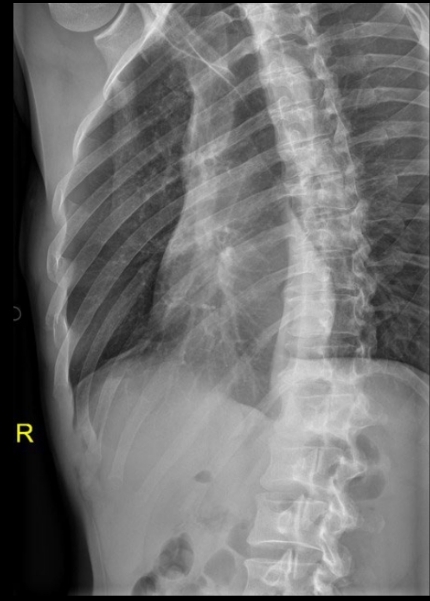

Qué se ve en una Rx de un hemotórax

• Derrame pleural

• Borammiento de la silueta cardíaca